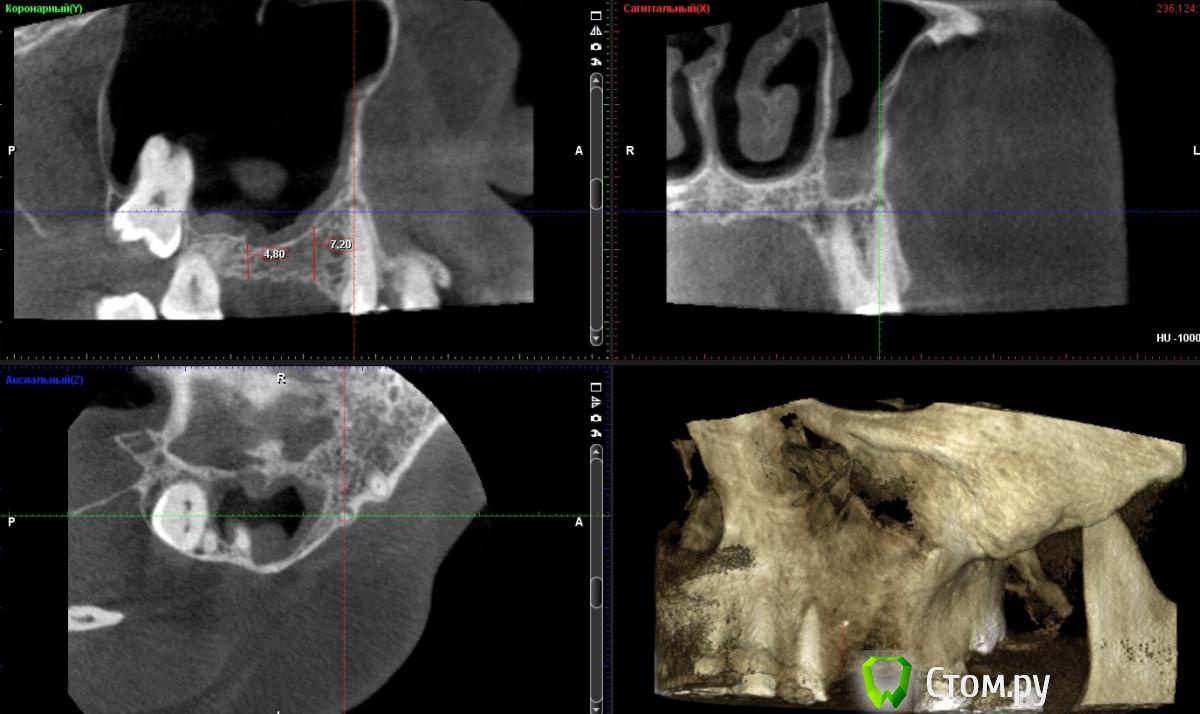

Andex Опубликовано 3 февраля, 2014 Поделиться Опубликовано 3 февраля, 2014 Приветсвую. Коллеги, есть такой случай. Сразу хочу сказать - интерестно обсудить только планирование в области 25-26 зубов. Про остальные "зубки" все понятно. Планирую имплантацию с закрытым синусом в области в позиции 25 и 26 зубов. Но есть одно "НО" - киста на щечном корне 24 зуба. Зуб никогда не беспокоил. Кисту нашел случайно-на 3Д. И вот теперь мысли - сильно ли я рискую, оставив все так как есть(просто проведя операцию), тк с одной стороны-киста нисчем не сообщается(с пазухой), с другой-это явный фактор риска при имплантации. Еще рассматриваю вариант - сделать одновременно с имплантацией цистэктомию апекса щечного корня 24, тк все равно буду отслаиватся в этой области - в таком случае, мои риски понизятся? Сразу скажу - удалять 24 не хочу. Спасибо за интерестные мнения) Ссылка на комментарий

Andex Опубликовано 5 февраля, 2014 Автор Поделиться Опубликовано 5 февраля, 2014 А сколько вы хотите поднять на закрытом в обл. 26 и какой длины имплантат собираетесь испольовать?Хотел бы поднять на 3 мм, имплант 4.2х10 Ссылка на комментарий

Andex Опубликовано 5 февраля, 2014 Автор Поделиться Опубликовано 5 февраля, 2014 Хороший ретрит думаю исправит состояние зуба 2.4Почему не хотите открытый синус проводить?Терапевт не взялась за перелечивание. Открытый не хочу, тк считаю что 4мм и 7 мм собственной кости вполне достаточные показания для закрытого, и после него сам сплю спокойнее,чем после открытого) Ссылка на комментарий

Артем Наймушин Опубликовано 7 февраля, 2014 Поделиться Опубликовано 7 февраля, 2014 По моему мнению было бы оптимально провести открытый синус лифитинг. Во время отслаивания провести цистэктомию с резекцией верхушки. Оболочка гранулемы/кисты, если оттесняет слизистую синуса, как правило не спаяна с синусом... Но всеравно аккуратность важна! Успехов) Ссылка на комментарий

bullbull Опубликовано 12 февраля, 2014 Поделиться Опубликовано 12 февраля, 2014 Терапевт не взялась за перелечивание. Открытый не хочу, тк считаю что 4мм и 7 мм собственной кости вполне достаточные показания для закрытого, и после него сам сплю спокойнее,чем после открытого)7 мм - да. 4 мм - сомнительно. Закрытым методом можно поднять на 4, максимум 5 мм.Может дело в финансовой составляющей для пациента? Ссылка на комментарий